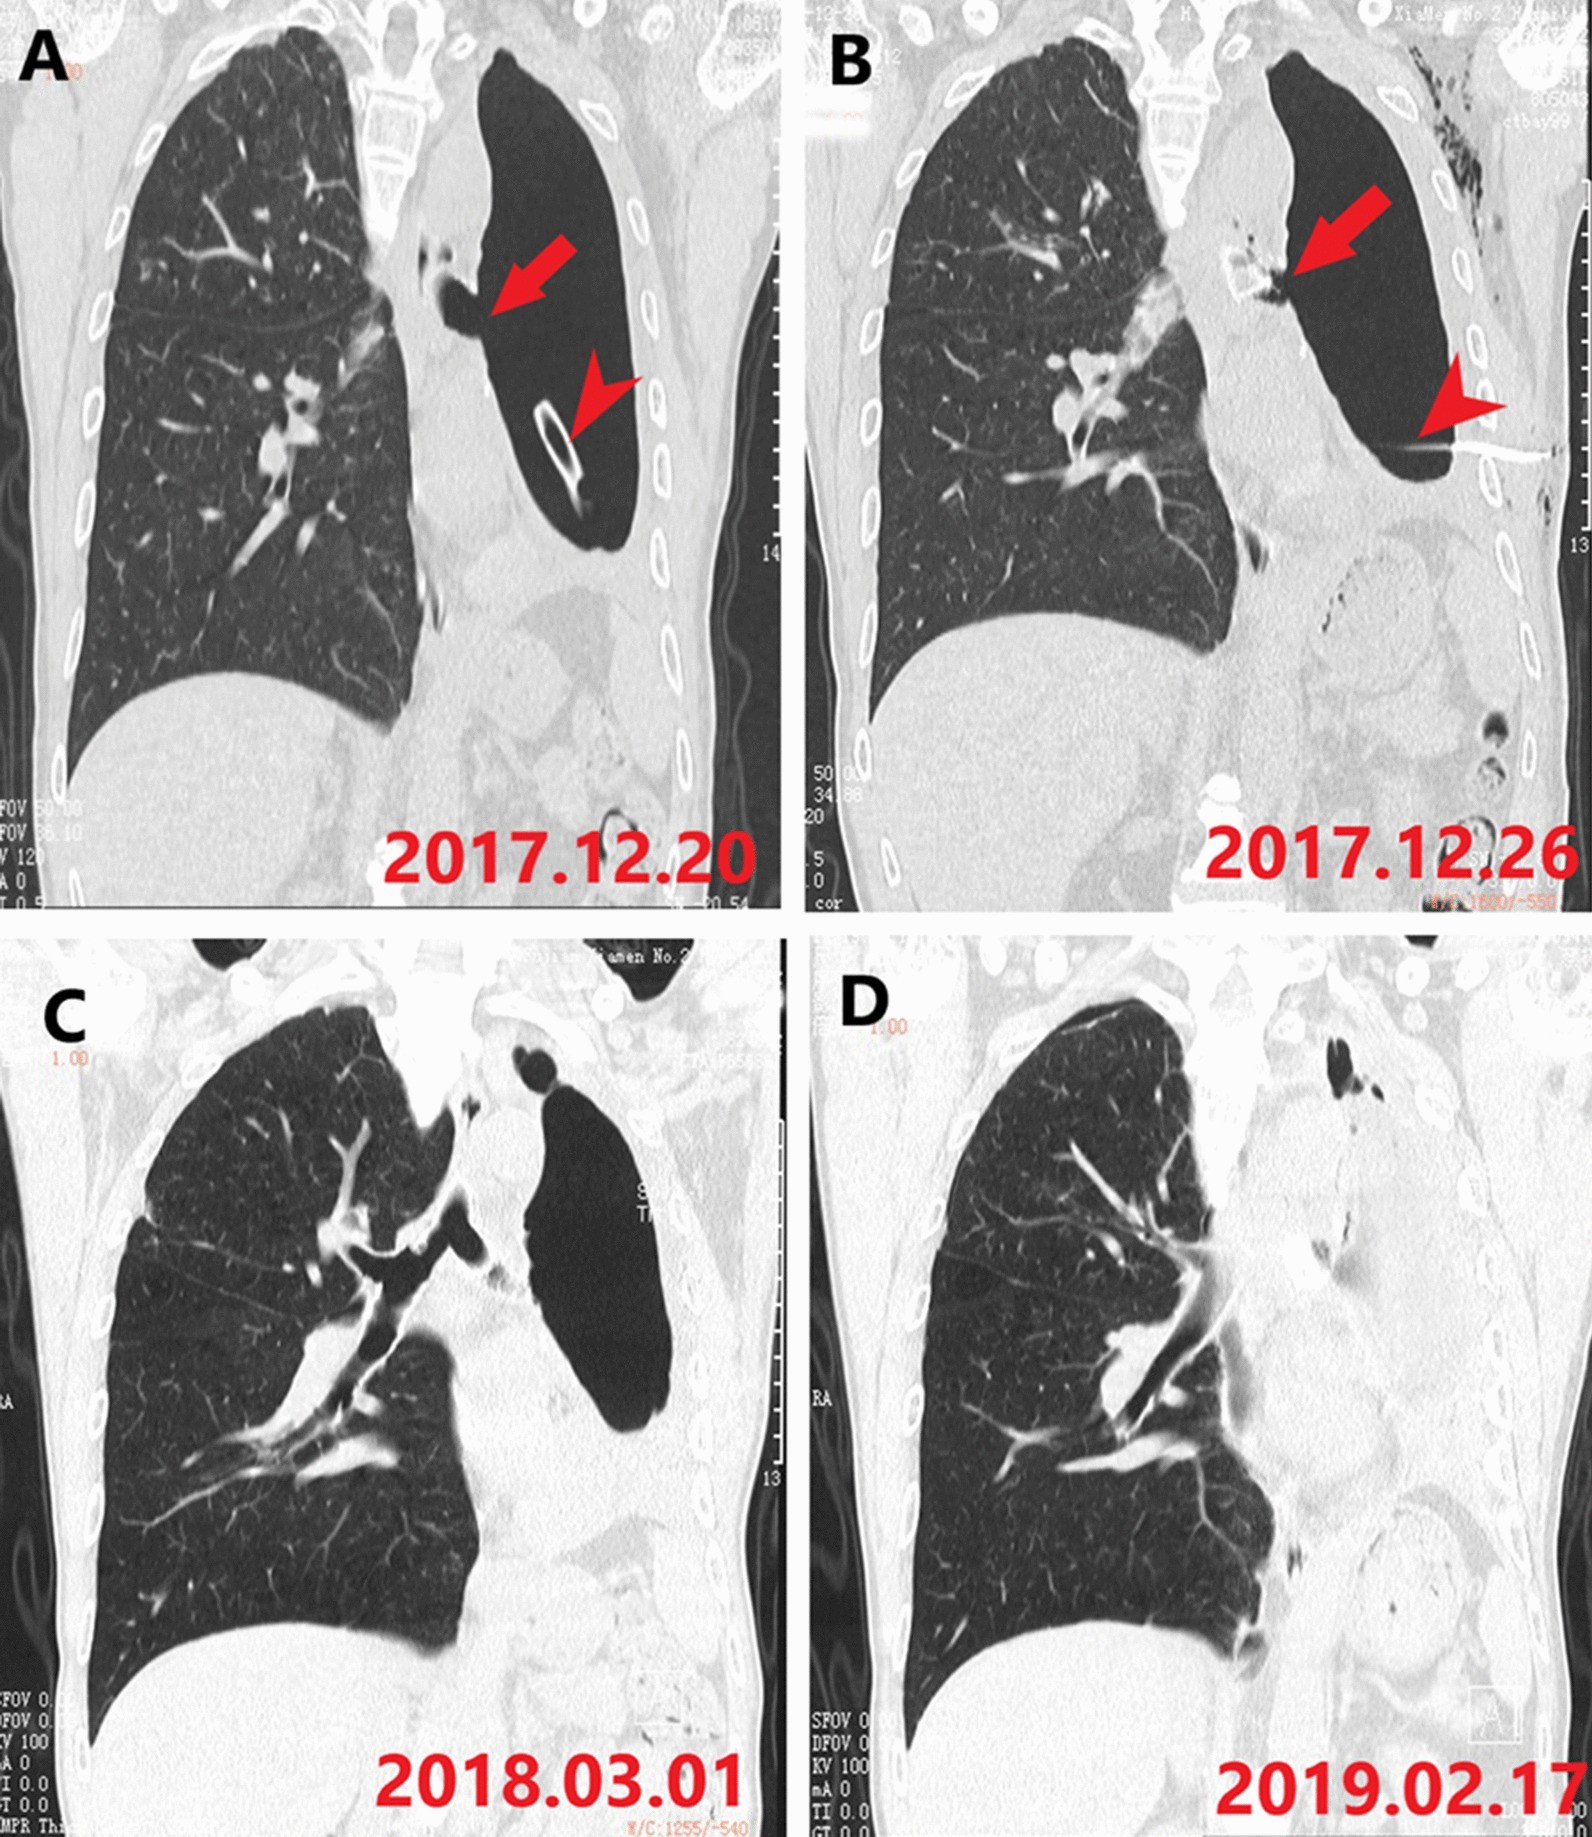

Fig. 4

The coronal computer tomography image of patient 5 in different time. a The fistula in the left main bronchus (arrow) and the drainage tube (arrow head) is placed in the left thoracic cavity; b the occluded branch of the stent can be seen in the left main bronchus (arrow) and the drainage tube (arrow head) is still in the left thoracic cavity; c the residual pleural space diminishes over time; d the residual pleural space disappears during follow-up